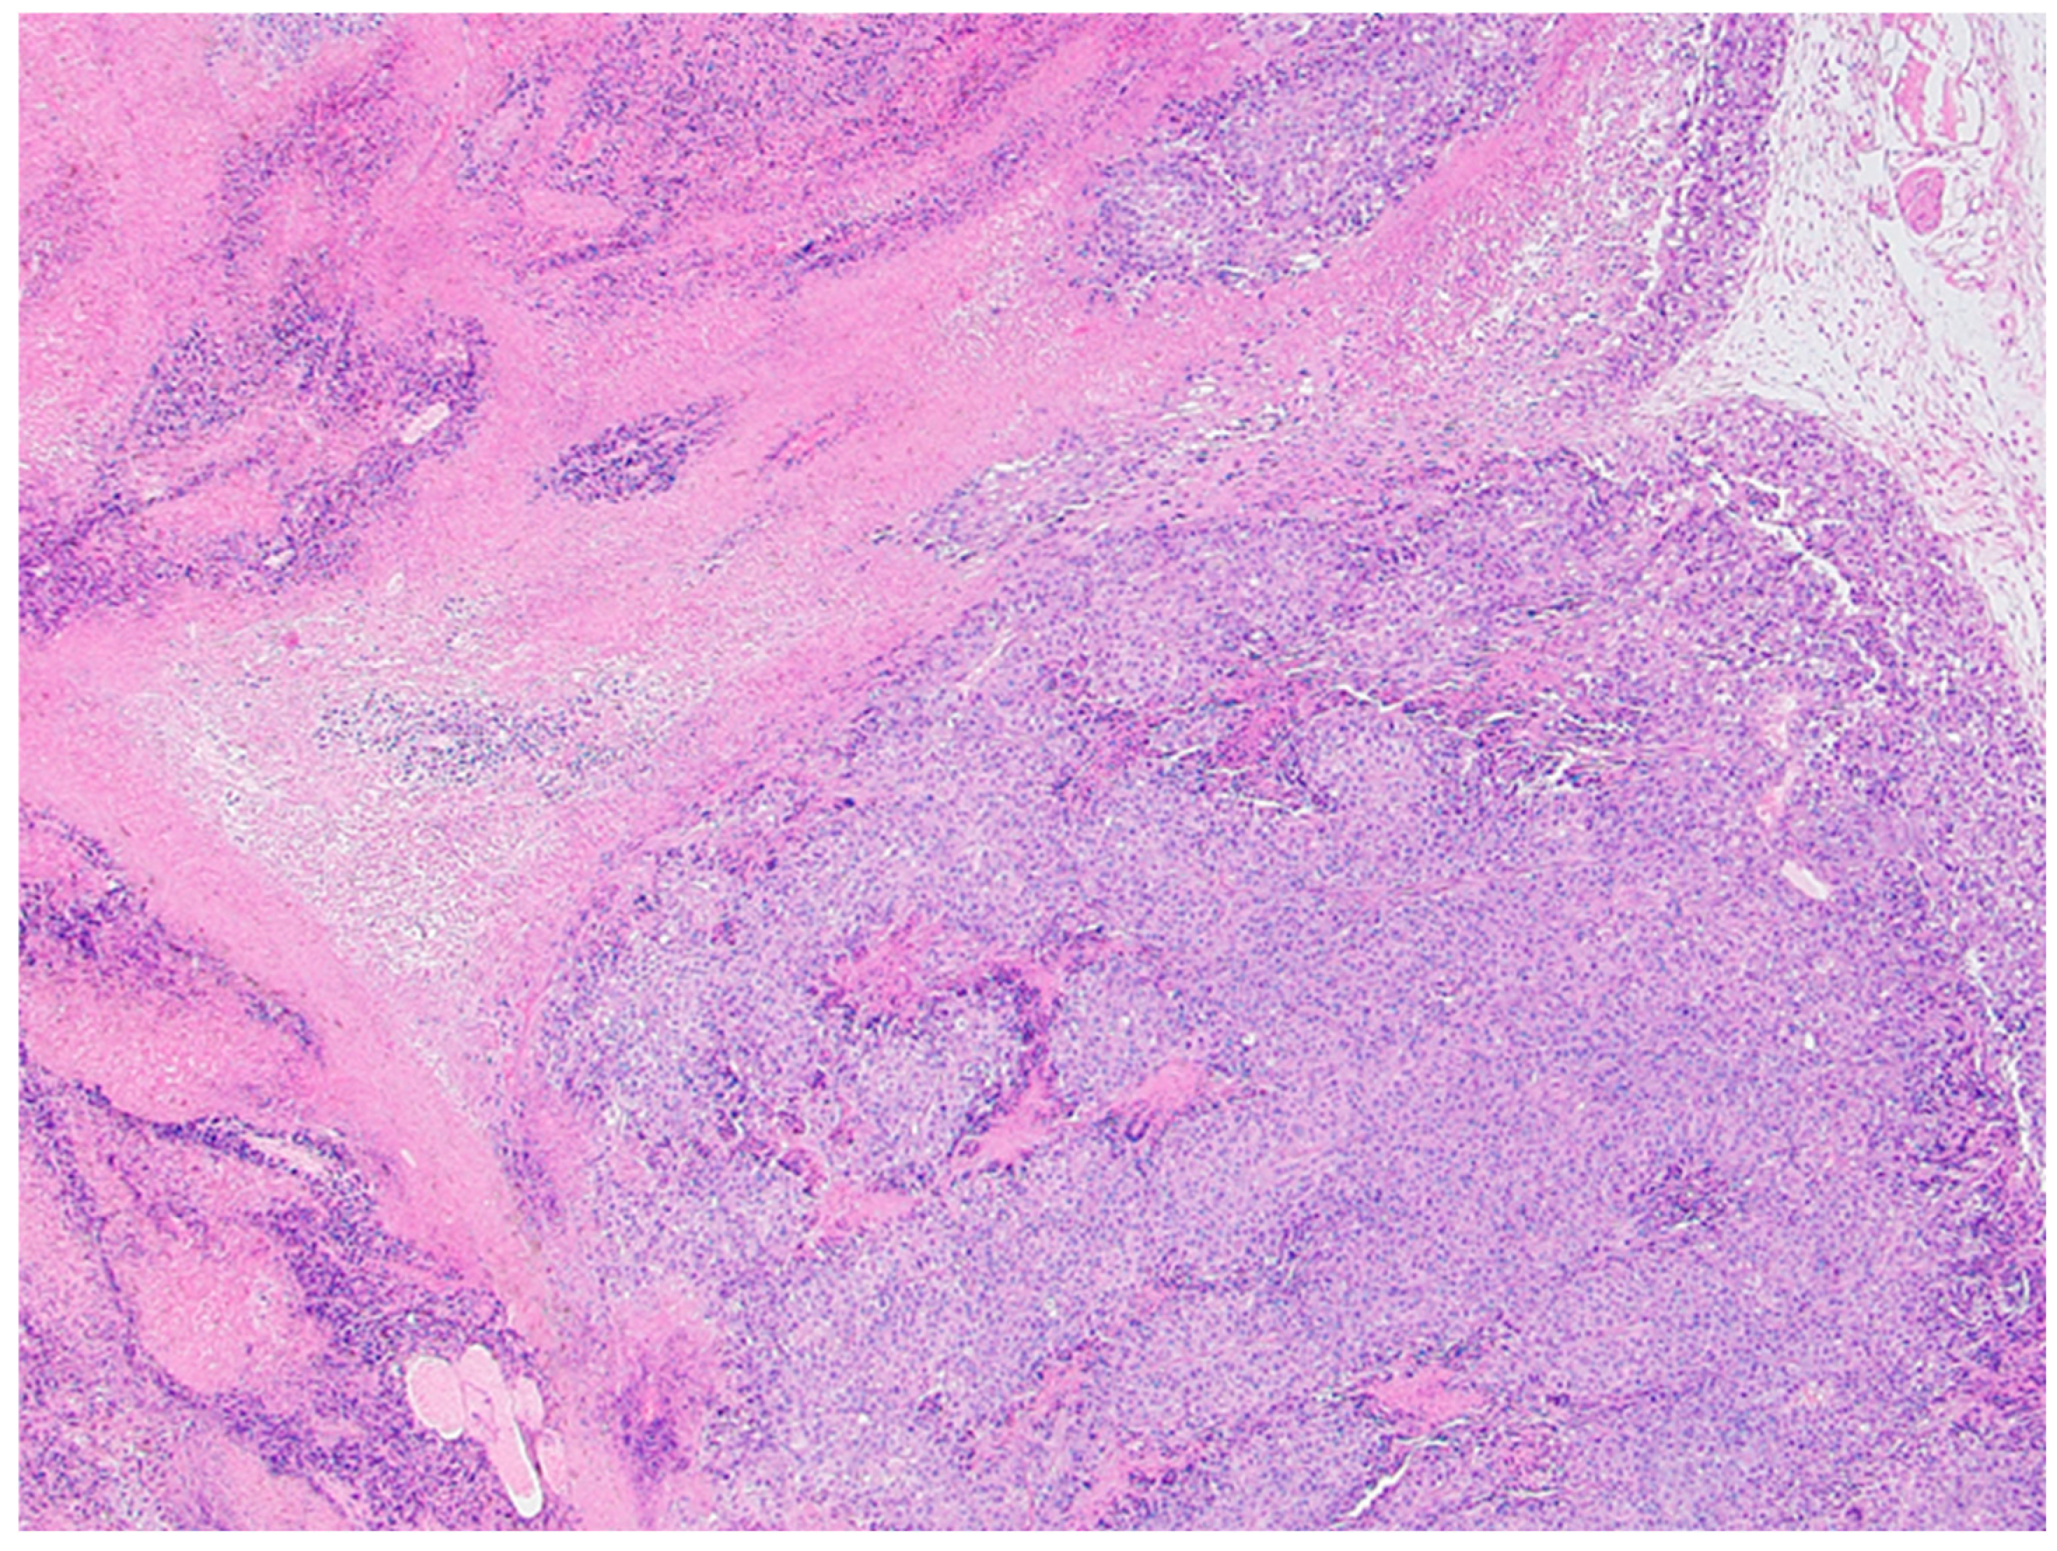

Histological analysis did not reveal overall and consistent differences between the xylitol and the vehicle groups. Indeed, the vehicle group demonstrated significant necrosis, perhaps due to the cancer growth. Tears or tracks were present in the xylitol samples, perhaps due to the xylitol injections. The vehicle injection group, however, did not demonstrate possible injection tracks (See Figures 3a and 3b).

Figure 3. a. Xylitol-treated tumor histology demonstrates slight, patchy intratumoral necrosis (i.e., high viable fraction in the tumor). Foci of degeneration/necrosis are marked (asterisks). Several stromal blood vessels – overall vascularity in the cancer is modest (arrowheads), with occasionally small hemorrhages (arrow). The section is from mouse 754 with 20% xylitol injections. Tears or tracks may represent areas where xylitol injections were placed and resulted in solution loss.

Figure 3. b. Vehicle-treated tumor representative image. Histology demonstrates extensive intratumoral necrosis (asterisks), resulting in ~60% viable fraction in tumor based solely on this image. Section from Mouse 765 with B16F10 melanoma tumor. Scattered stromal blood vessels are present, and overall vascularity in the tumor is low (arrows)—blood vessels in viable (solid arrow) and necrotic (open arrows) areas.